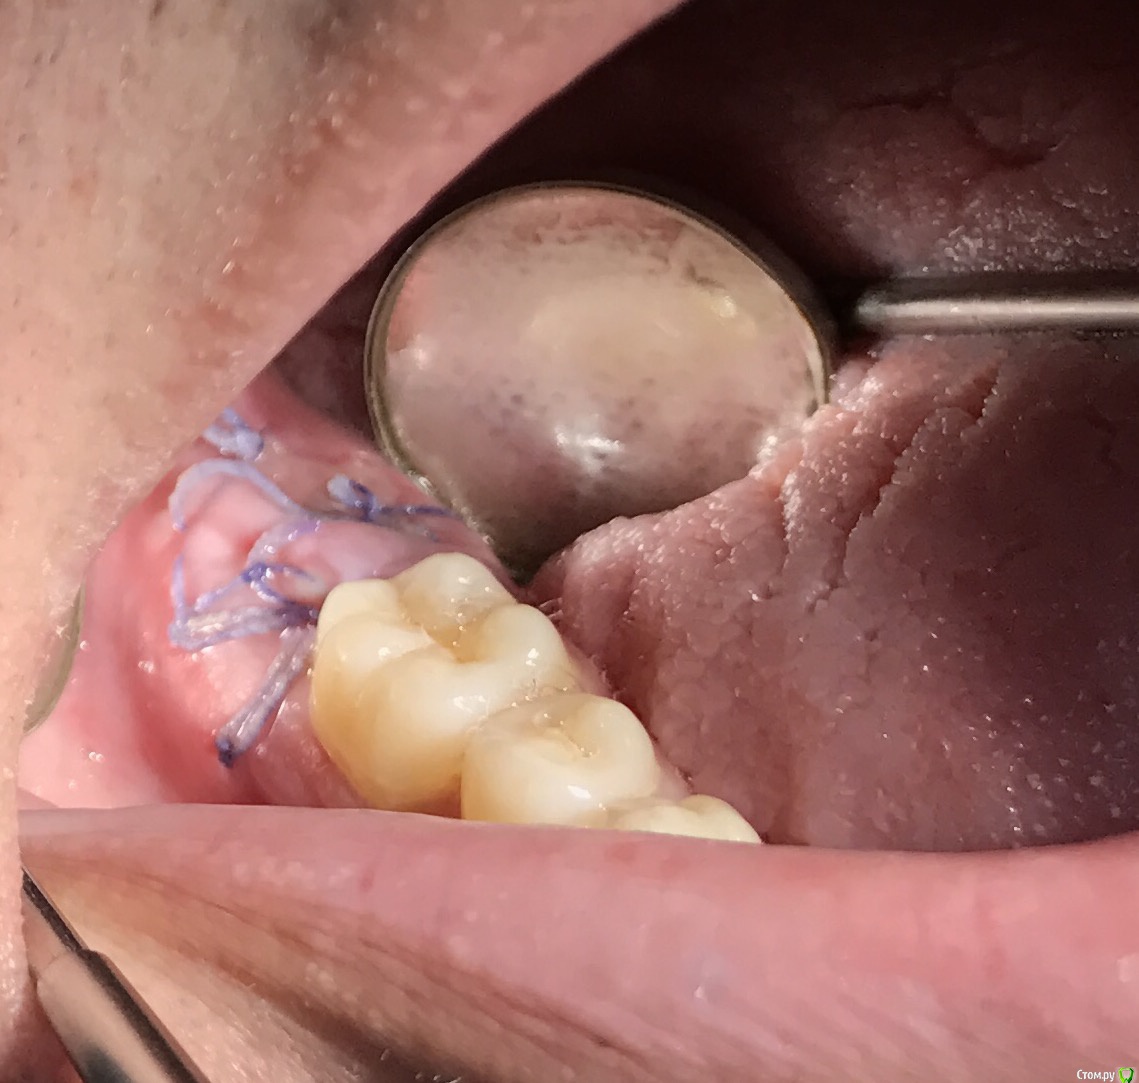

колесников Опубликовано 3 августа, 2019 Автор Поделиться Опубликовано 3 августа, 2019 27ой закрыт «бугром на ножке»,вид через неделю. Всем рекомендую 1 Ссылка на комментарий

колесников Опубликовано 8 августа, 2019 Автор Поделиться Опубликовано 8 августа, 2019 Ещё о перемещении бугра 2 Ссылка на комментарий